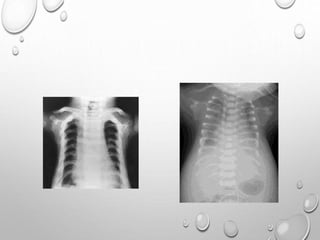

• AP & lateral skull to

include atlas & axis

• AP chest

• AP pelvis

• AP lumbar spine

• Lateral

thoracolumbar spine

• AP one lower limb

• AP one upper limb

• Postero-anterior

(PA) one hand

(usually left for bone

age assessment)